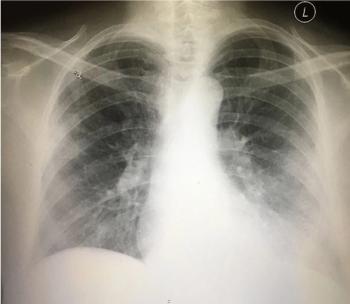

Patient's vital signs and results of physical examination are normal; results of a previous lumbar puncture also were normal. What does the chest x-ray reveal?